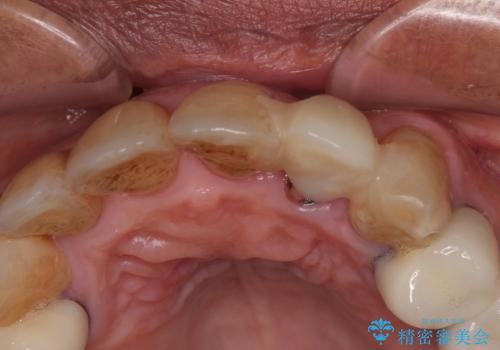

診察をしたところ、歯根に縦破折が認められ、抜歯が必要と判断されました。

抜歯、インプラント埋入、仮歯の装着が同時に可能な1DAYインプラントが適用可能と判断されたため、インプラントによる補綴治療を行うこととしました。